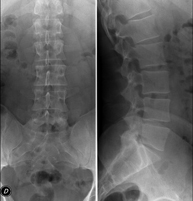

- Lumbar spine X-ray

This technique uses X-ray rendered imaging to examine the lumbar spine. Indicated for: sciatica, trauma, lower back pain.

- Spinal teleradiology

This technique uses X-ray rendered imaging to examine the entire spinal column, especially assessing the presence of scoliosis and pelvic dysmetria.